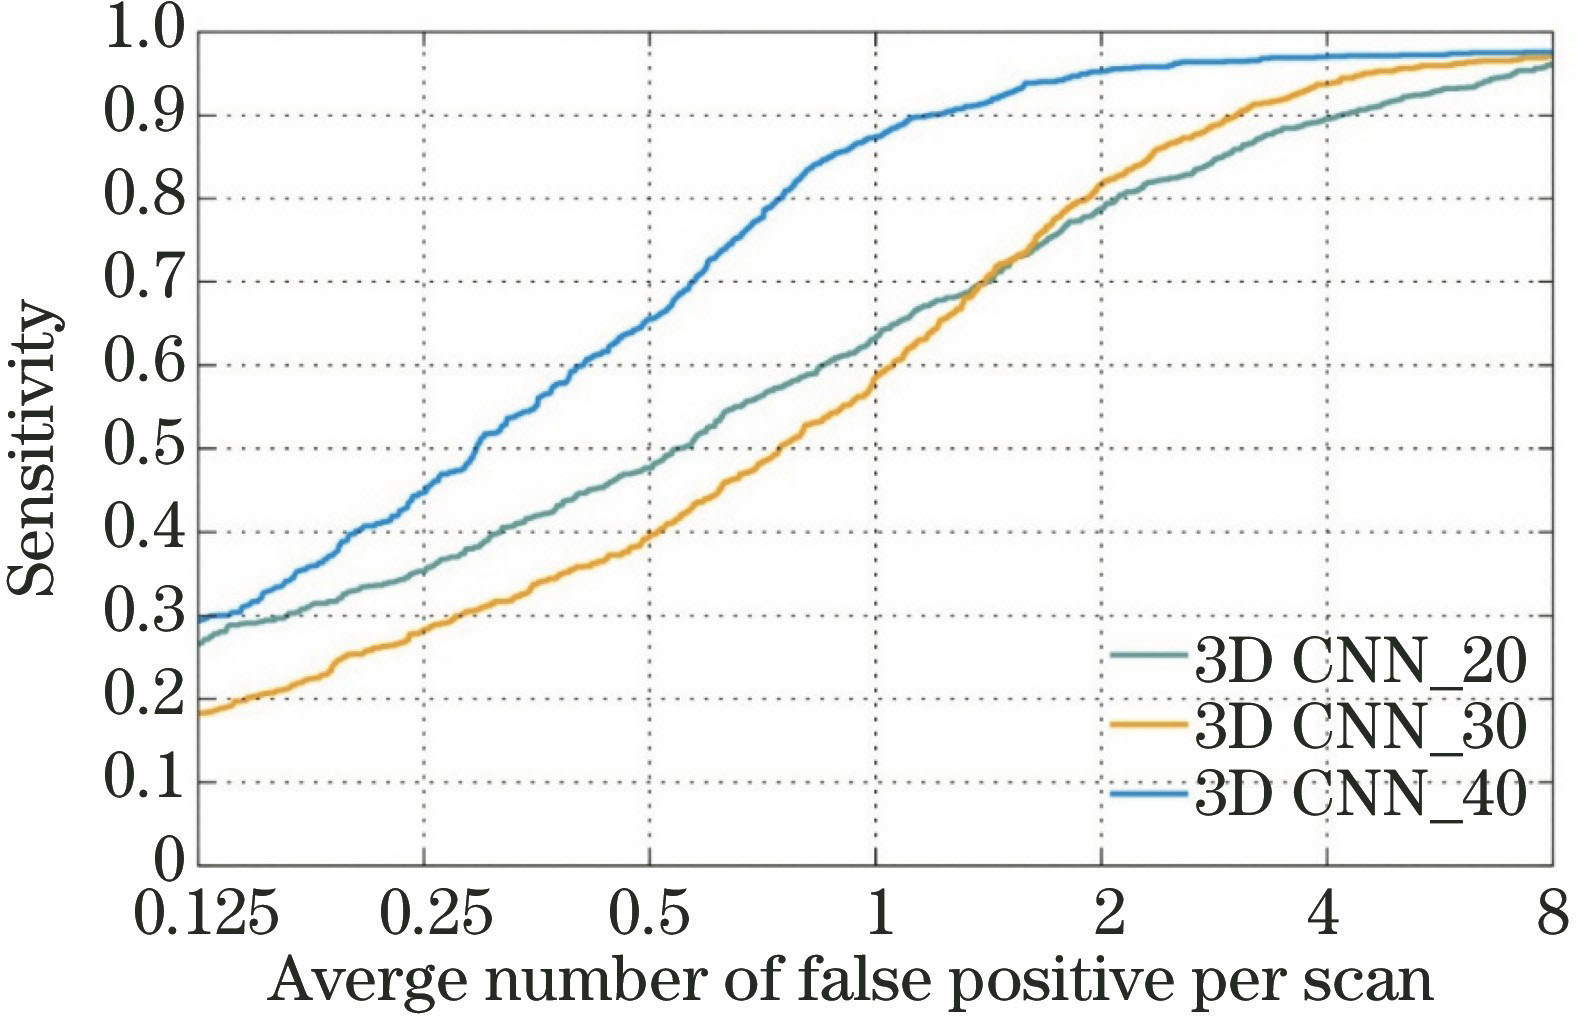

图 8. 输入图像块的尺度对实验结果的影响

Fig. 8. Effect of the dimensions of the input image block on the experimental results